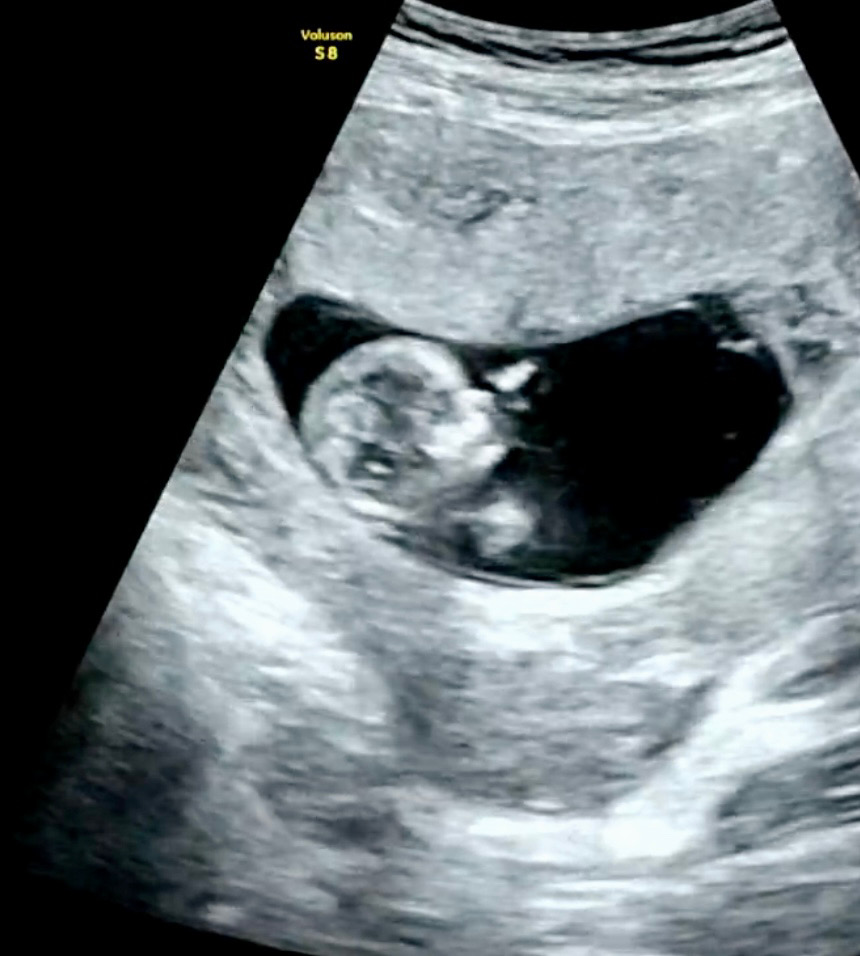

12주 입성~

어제 11주 6일차 촘파로 만난 땡큐 옆모습이에요! (5.52cm/156bpm/12주 1일 크기) 마치 손가락 말아 쥐고 “엄마 힘내”라고 외치고 있는 느낌이랄까요 ㅎ (병원에서 받은 동영상을 0.1초 단위로 조절하며 찾았다는 건 비밀로 할게요 ^^;) 의사쌤이 점점 초음파로 전신을 다 보기 어려워진다고 하시던데.. 꼬물꼬물 하는 모습을 보고 싶었는데 조금은 아쉽네요 ㅎㅎ 요즘 와이프가 입덧이 심해서 그나마 먹을 수 있는 게 과일인지라 과일을 아침저녁으로 매일 먹었는데, 과일을 많이 먹으면 빨리 큰다는 얘기가 있어서.. 혹시나 너무 빨리 크진 않았을까 걱정을 좀 했었거든요. 그런데 어제 보니 주수에 맞게 잘 크고 있다고 해서 조금은 안심하고 돌아왔네요 ㅎㅎ 모두 즐거운 하루 시작하세요!!